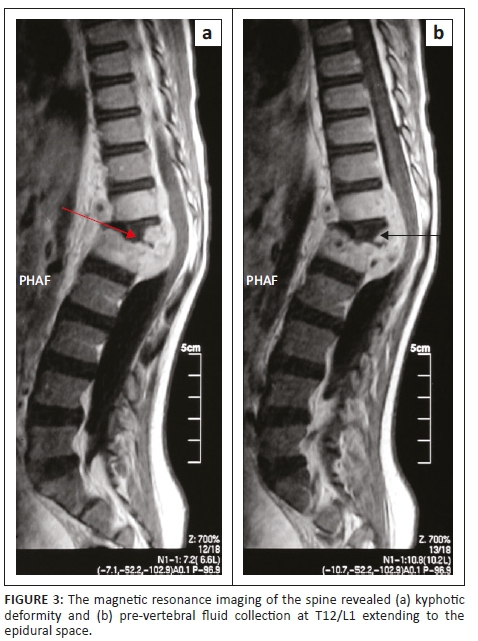

Magnetic resonance imaging of the entire spine revealed features suggestive of tuberculosis infection (Figure 3). There was kyphotic deformity and pre-vertebral fluid collection at T12/L1 extending to the epidural space. The fluid collection was low on T1, high on T2 and became enhanced post-contrast. There was also an abnormal signal of L1 and T12, as well as associated involvement of the superior end plate of L1. The T12/L1 intervertebral disc was not clearly delineated with the distortion of normal anatomy. Spinal canal stenosis was observed at the level of kyphotic deformity with cord compression, although there was spinal cord edema. Posterior elements were preserved and facet joints were normal (Figure 3).